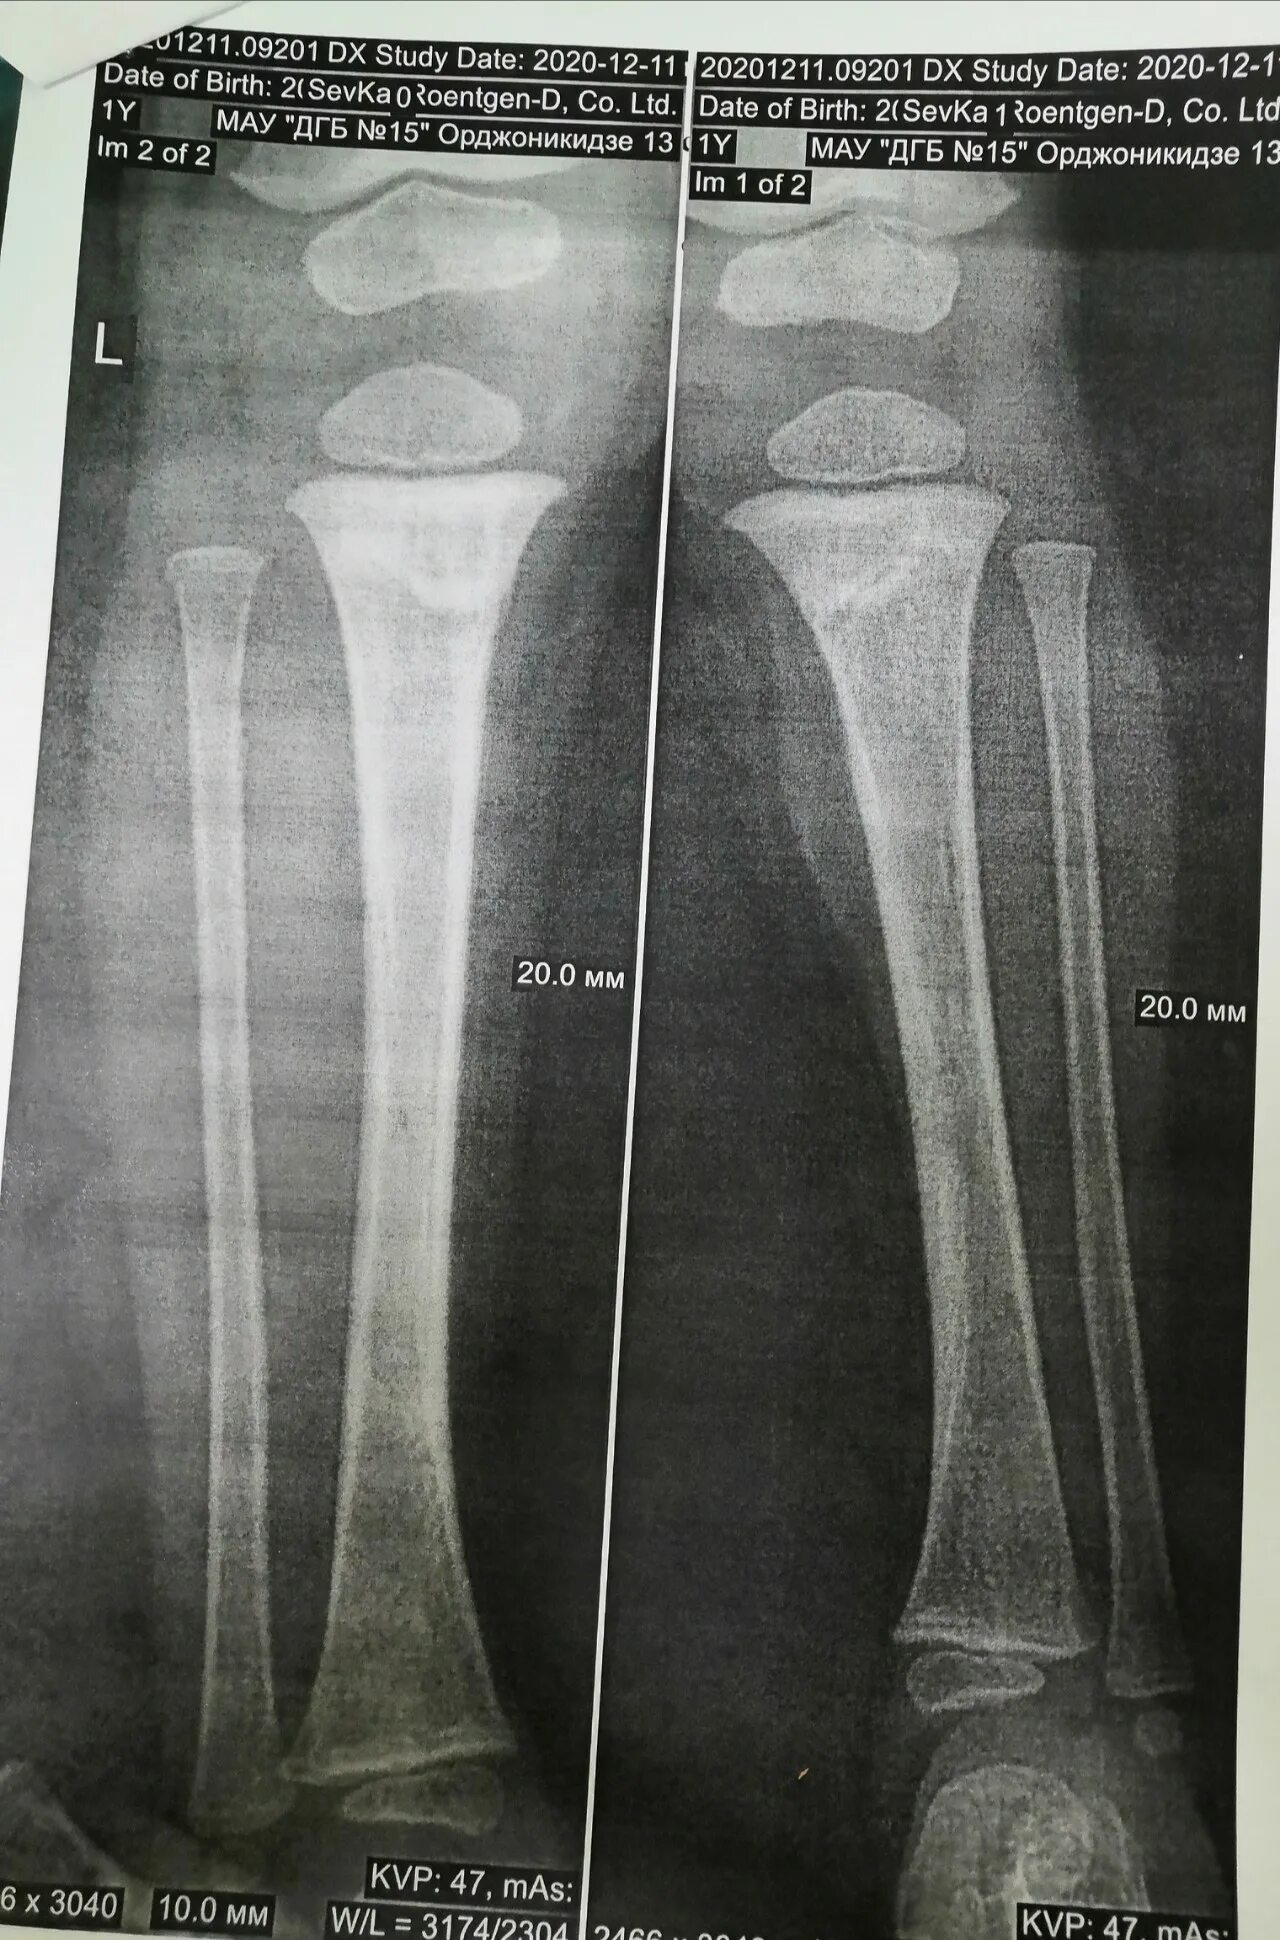

Сколько срастается малая берцовая кость